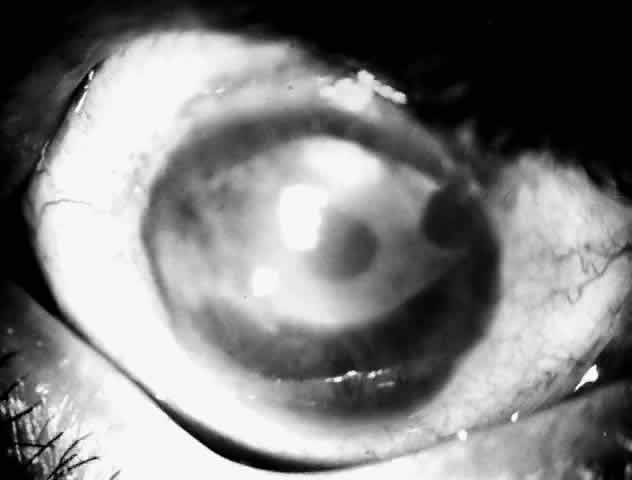

Active corneal infections in advanced stages are encountered more often by corneal surgeons in developing countries compared with their counterparts in developed countries (Fig. 8). The extent of corneal involvement associated with other intraocular damage often compromises the success of corneal transplantation. In a series from our institution, the success rate for graft clarity was poorer24 compared with other series.25 Ophthalmologists involved in corneal surgery should be familiar with this information and be prepared for the necessary intraoperative manipulations (Fig. 9).

Fig. 8. Corneal ulcer with extensive necrosis and perforation in the superior part.

Fig. 9. Large central perforation in a case of infectious keratitis.